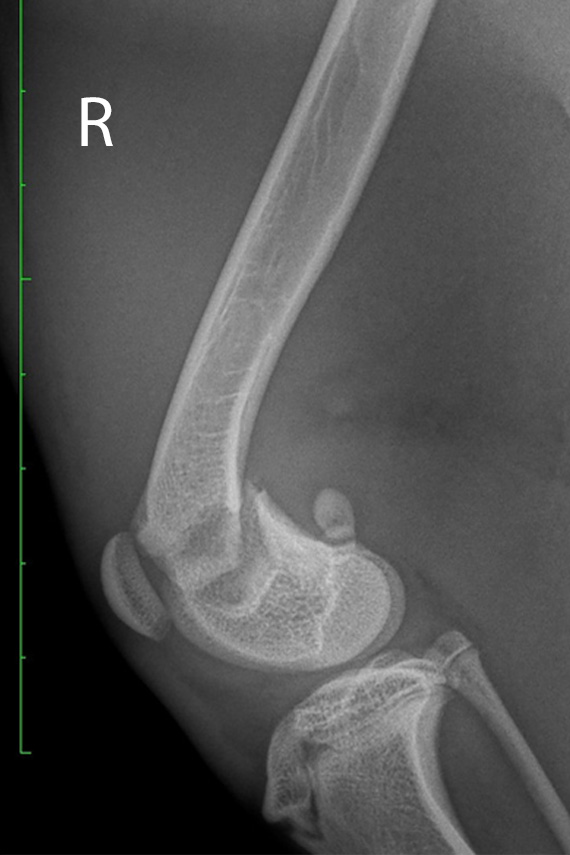

Salter Harris Fraktur

Wachstumsfugenfraktur (Salter Harris Fraktur) am distalen Femur bei einem Hund

Versorgung der Fraktur mit Pins

Salter Harris Fraktur post-operativ

Kontrollröngtenaufnahme in der 2. Ebene.